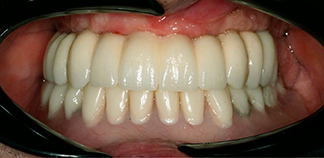

До лечения

Пациент обратился с просьбой заменить съемные протезы на несъемные.

Как лечили

Проведено протезирование по протоколу «All-on-4» на верхней челюсти и съемное протезирование на двух имплантах на нижней челюсти.

Лечащие врачи

МАРКОСЯН Геворк Сандроевич, ТИГРАНЯН Варангюл Гургенович